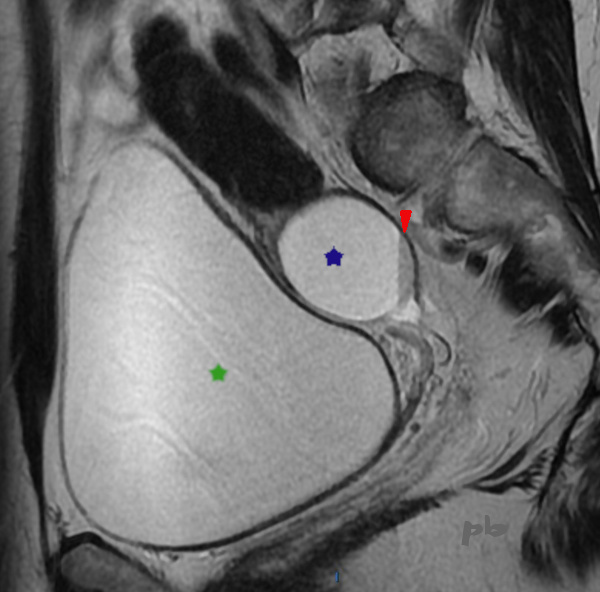

16 – Diagnostic différentiel – Kyste hémorragique fonctionnel (même patiente que 15)

IRM le 17/8 pour confirmation de l’adénomyose (et non pour le kyste ovarien, typique d’une origine fonctionnelle en écho) : adénomyose confirmée (non montrée), et kyste ovarien droit fonctionnel hémorragique (★).

Sédiment hématique en signal T2 intermédiaire (►) et hypersignal T1 (non montré).

Vessie pleine (★).

Echo le 15/11 : disparition du kyste, confirmant son origine fonctionnelle.